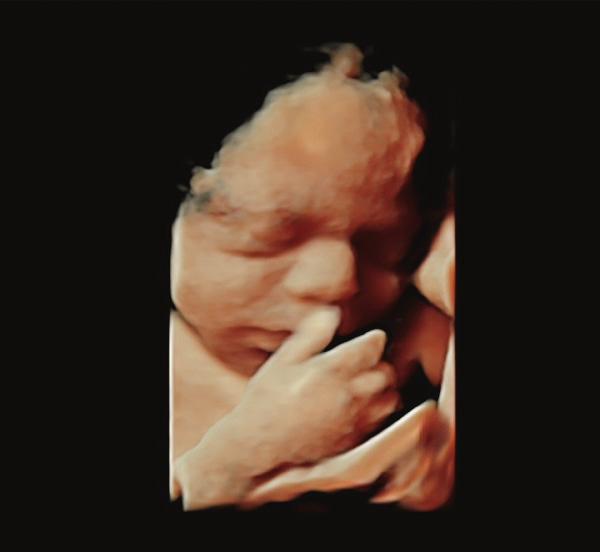

Detaylı ultrason, ikinci düzey ultrason ve ayrıntılı ultrason aynı anlama gelir. Renkli ultrason veya 4 boyutlu ultrason detaylı ultrasonla aynı şey değildir. 4 boyutlu ultrasonda bebeğinizin yüzü veya organlarının güzel bir anı olarak saklanacak fotoğrafı alınır. Detaylı ultrasonda ise bebeğin bütün organları ultrason teknolojisi el verdiğince incelenir

Detaylı ultrasonun yapıldığı cihazın görüntü kalitesi çok iyi olmalıdır. Ayrıca detaylı ultrason için kullanılan cihazın doppler özelliğinin olması gerekir. Yüz gibi bazı kısımlar iki boyutlu ultrasondan ziyade dört boyutlu ultrasonla daha iyi değerlendirilir.

- Bebeklerin genel yüz profilleri, burun kemikleri ve gözlerinde bulunan lenslerin izlemesi yapılır.